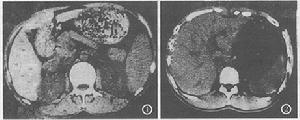

(4)影像學檢查:用B型超音波檢查華支睪吸蟲病患者時,可見肝內光點粗密欠均,有小斑片或團塊狀回聲,瀰漫性中、小膽管不同程度擴張,膽管壁粗糙、增厚、回聲增強。在1528例華支睪吸蟲病患者B型超音波檢查時發現肝膽系異常變化的有210例,占總數13.3%。其中肝內小膽管壁回聲增強120例,膽管壁增厚25例,膽石22例,膽囊異物7例,肝癌3例,脾臟大45例,儘管聲像圖無特異性,但仍具一定參考價值。

CT檢查華支睪吸蟲患者時,可見肝內膽管從肝門向周圍均勻擴張,肝外膽管無明顯擴張;肝內管狀擴張,膽管直徑與長度比多小於1∶10;囊樣擴張的膽小管以肝周邊分布為主,管徑大小相近。少數病例膽囊內可見不規則組織塊影。